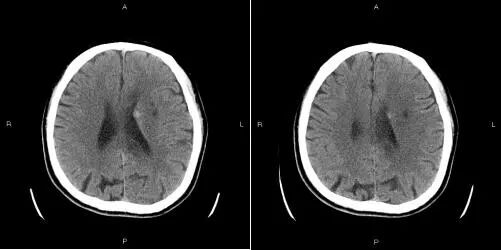

患者术后无任何不适。术后第一天复查颅脑CT发现左侧脑室旁少量渗血,停用盐酸替罗非班,考虑渗血面积较小,继续双抗治疗。

术后第二天复查颅脑CT渗血面积无增大密度略减低,继续双抗治疗。